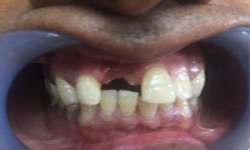

(4) Diastema Closure

Before Treatment

After Treatment

Patient with a complaint of a gap in between upper central incisors. Dental Veneers done to close the gap between the central incisors